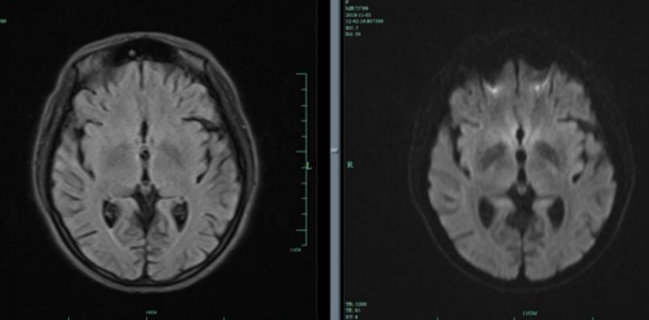

患者男,52岁,因“幻觉胡言 乱语3天,伴视物重影2天”入院。

答案:韦尼克脑病。易受到硫胺素(维生素B1)缺乏造成的损害的部位包括丘脑、乳头体、导水管周围和室旁区域、蓝斑、 颅神经核和网状结构。临床表现包括以下三个症状:眼肌麻痹、共济失调和脑病症状精神状态或智能状态改变。